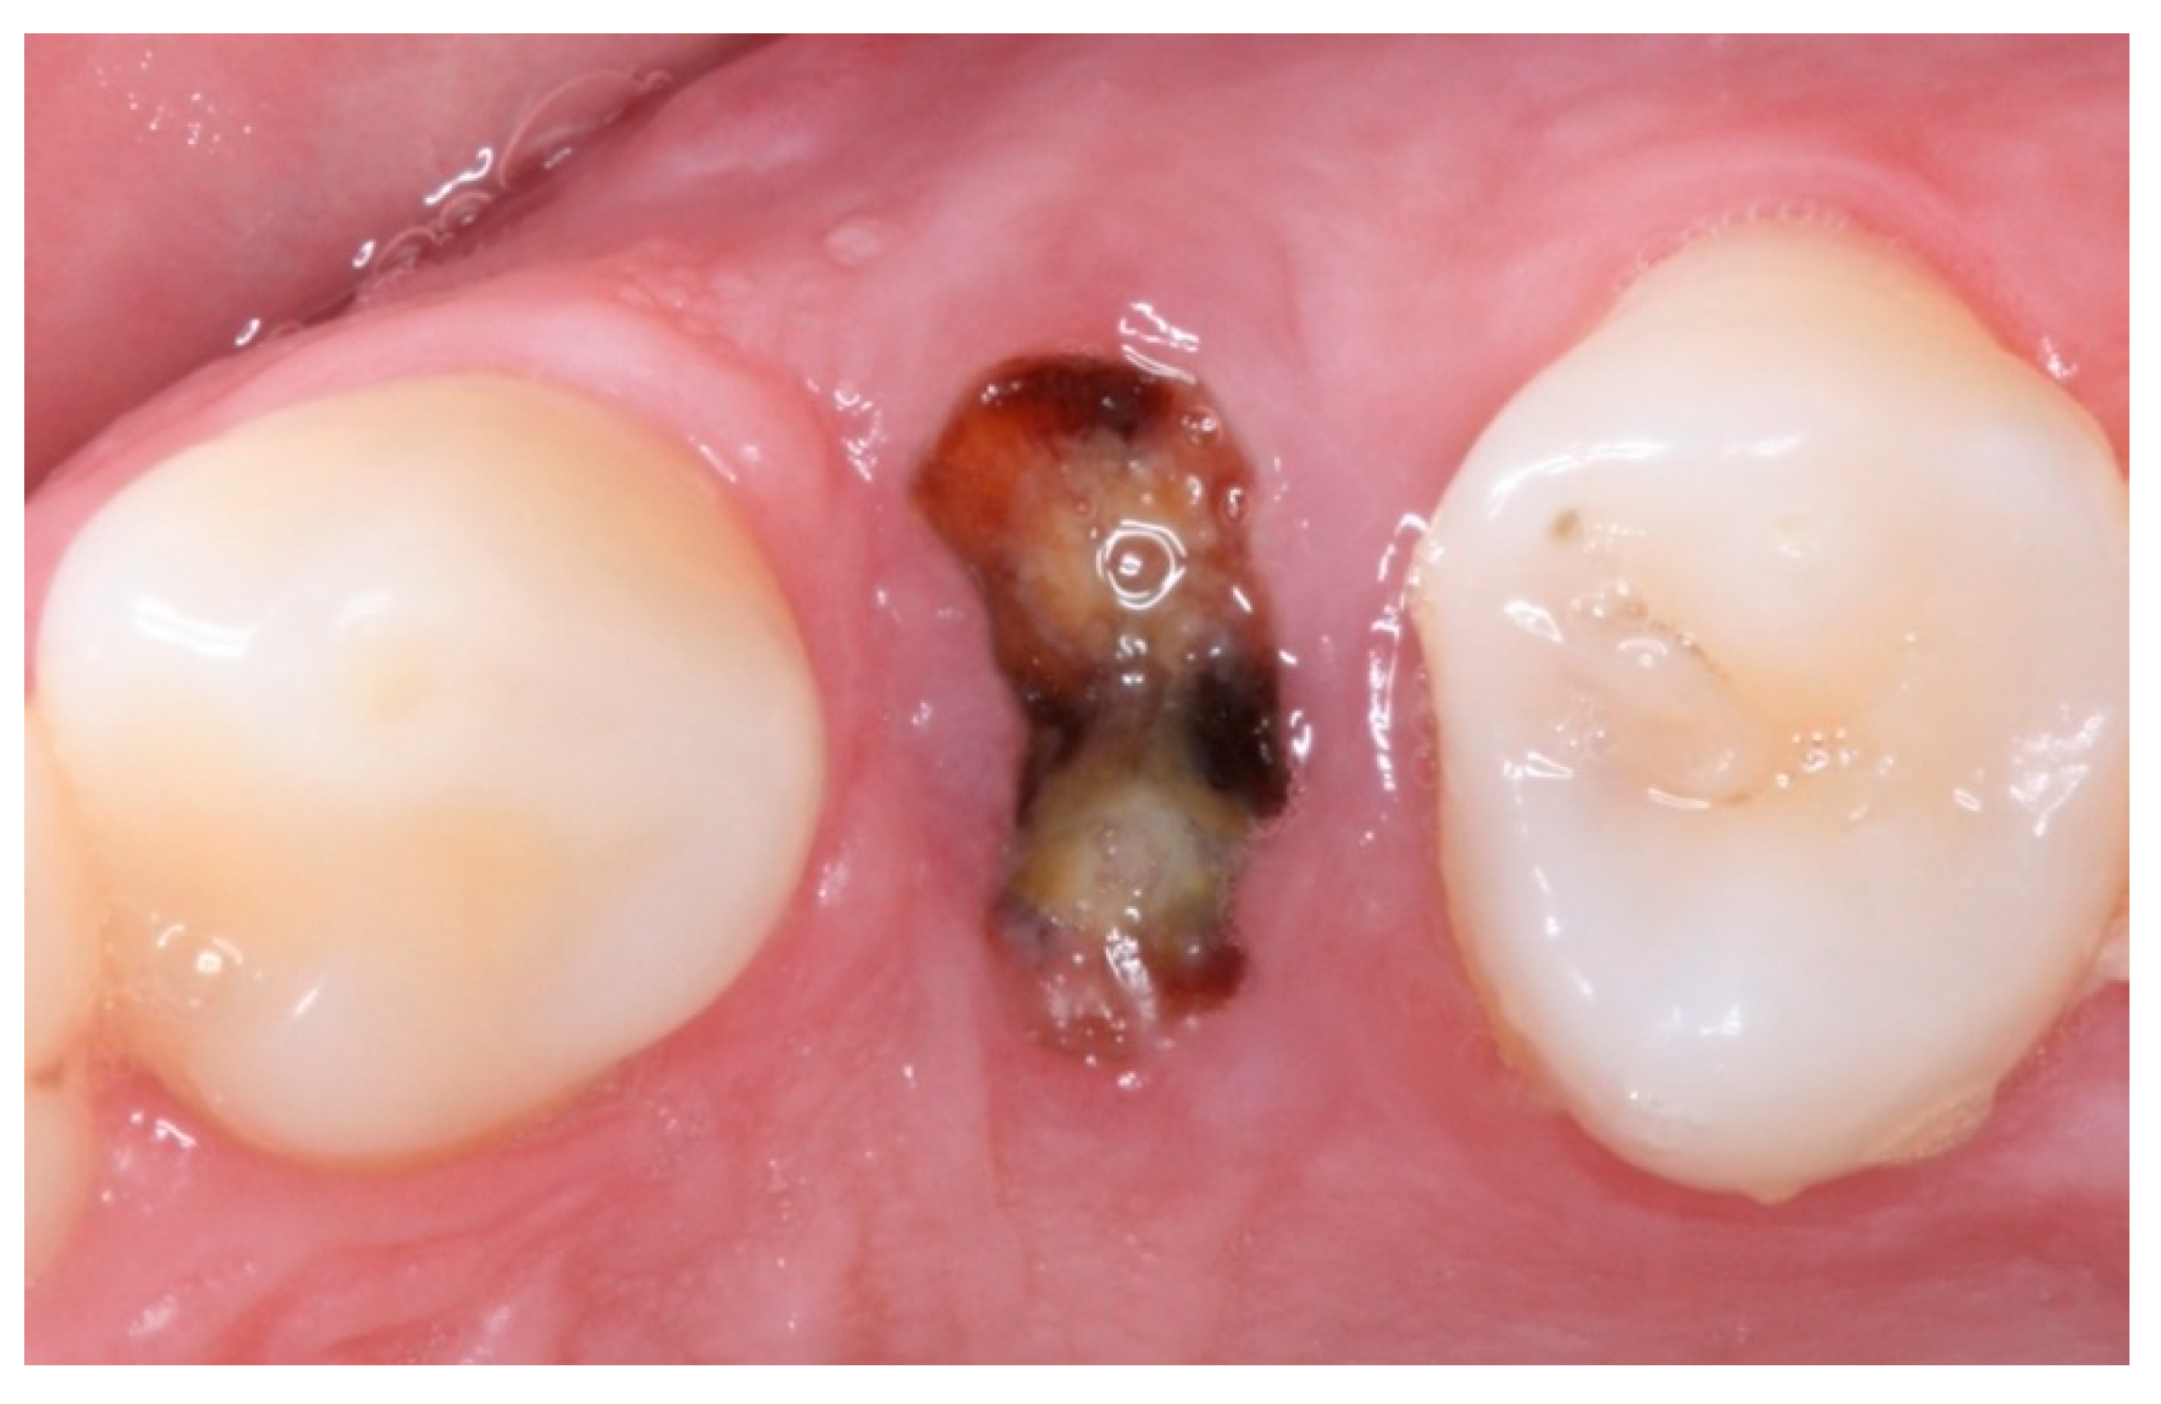

2. Materials and Methods

2.1. Study Population

2.2. Inclusion and Exclusion Criteria